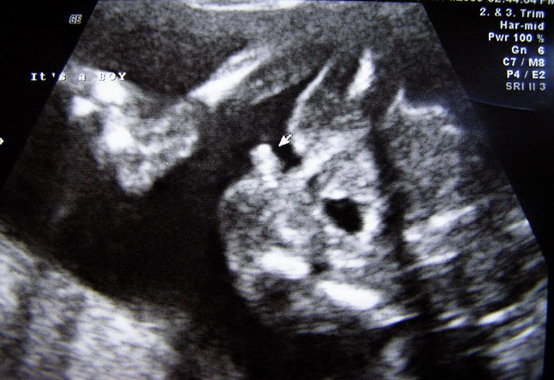

Hetfo ota mar biztosan tudjuk, hogy fiunk lesz!!! Eddig ugy tunt hogy kislany, am kiderult, hogy csak jol megviccelt minket de most mar nincsenek ketelyeink. Kaptunk egy szep kukis UH kepet is, ugyhogy semmi ketseg :) .

Na es a kepek: a kukis es egy profil ahol eppen a mehlepenyt szopogatta...